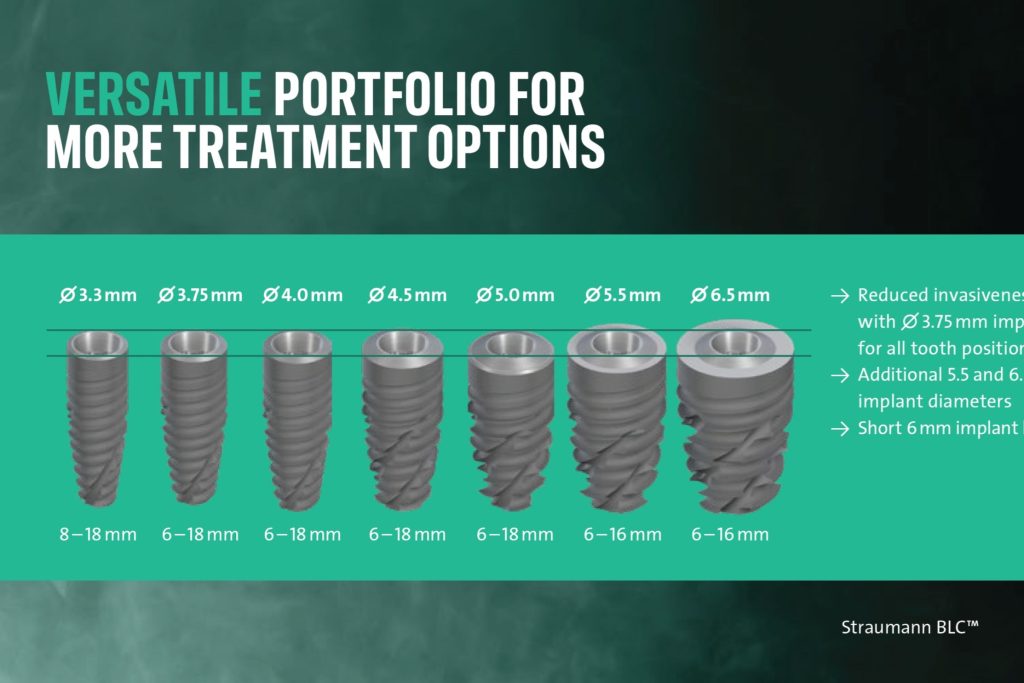

Димензије имплантата

Имплантни систем мора да обухвати све могуће индикације, од кратких имплантата дужине 4 мм до дугих имплантата дужине 25 мм. Пошто је индикација за кратке имплантате очигледна, желимо да избегнемо оштећење анатомских структура; дуги имплантати помажу да се досегну критичне плоче и обезбеде стабилне позиције имплантата чак и у меком кости. Без дуги импланти Немогуће је извршити прави All-on-4 третман.

Пречник имплантата такође треба да варира од веома уског од 2,9 мм до широког пречника од 5, па чак и 6 милиметара.

Иако постоји широк спектар пречника, платформа треба да буде иста ради практичности. То значи да можете користити један абатмент за све пречнике имплантата.

- Свеобухватне димензије: Систем мора да обухвати све анатомске потребе, од уских пречника од 2,9 мм до дужина до 25 мм. Без имплантата дужих од 16 мм, немогуће је постићи поуздан Све на 4 рестаурација са правилним антеропостериорним (АП) распоредом потребним за стабилност.